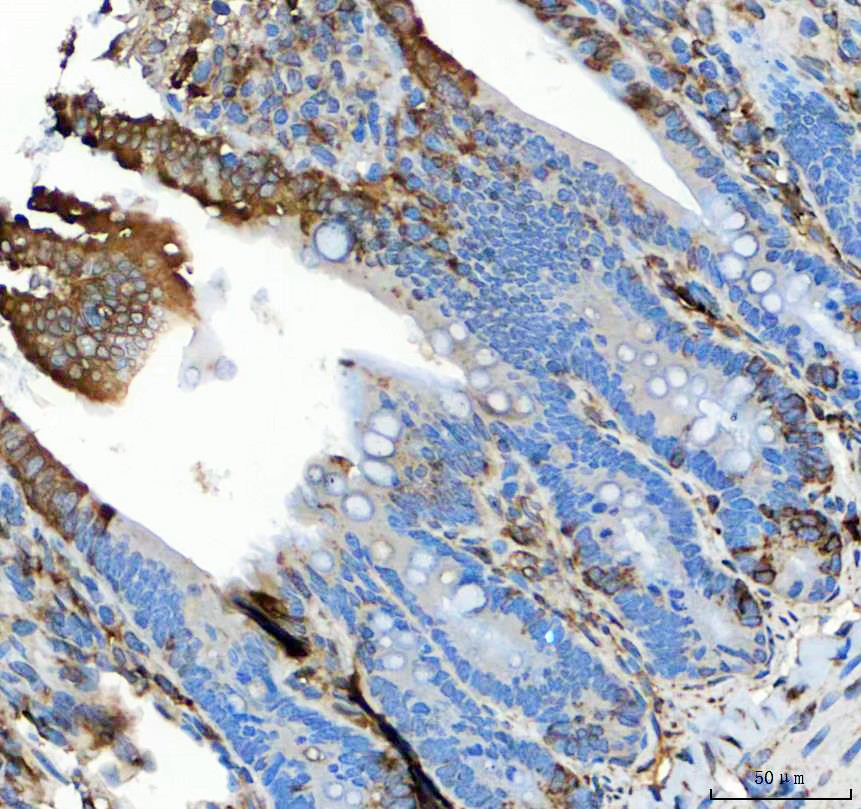

IHC analysis of GRP78/BIP/HSPA5 using anti-GRP78/BIP/HSPA5 antibody (PB0669) .

GRP78/BIP/HSPA5 was detected in a paraffin-embedded section of rat colon tissue. The tissue section was incubated with rabbit anti-GRP78/BIP/HSPA5 Antibody (PB0669) at a dilution of 1:200 and developed using HRP Conjugated Rabbit IgG Super Vision Assay Kit (Catalog # SV0002) with DAB (Catalog # AR1027) as the chromogen.